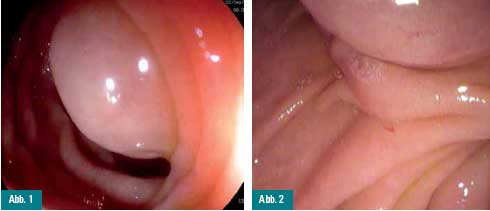

Eine 26-jährige Patientin wird wegen

rezidivierender abdomineller Schmerzen gastroskopiert. Neben einer

geringgradigen Antrumgastritis findet sich als auffälligster Befund eine

submuköse Vorwölbung im Bereich des oberen Duodenalknies. Nach dem

Wechsel auf ein Duodenoskop mit Seitblickoptik lässt sich die Läsion

deutlich von der Papilla major abgrenzen (Abb. 1 und 2).